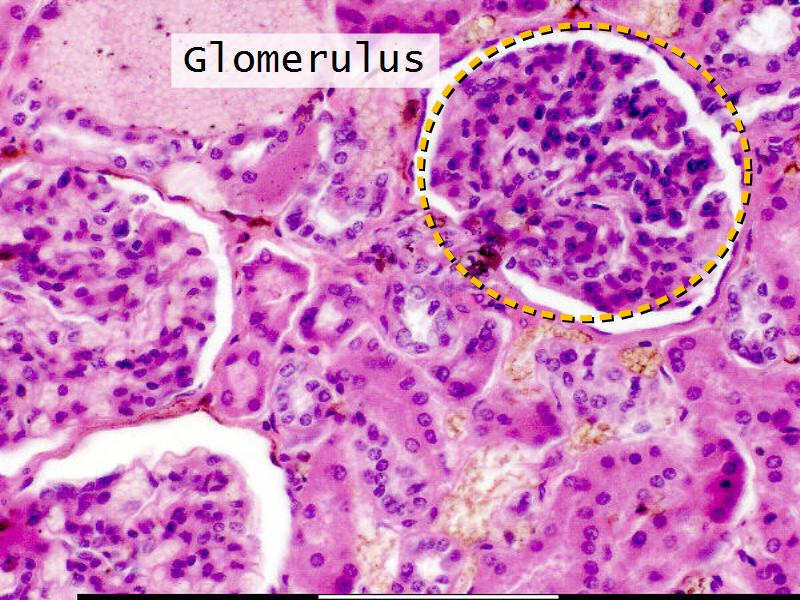

- The renal corpuscle

Nephron